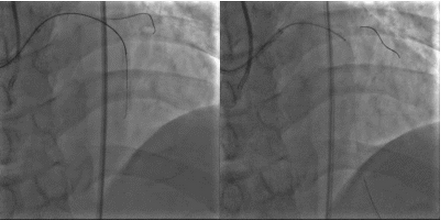

2015年10月23日:左主干远段30%狭窄;左前降支近段支架自开口完全闭塞;左回旋支中段长病变,狭窄40%~50%,高位钝缘支粗大,未见狭窄(图1)。右冠粗大、优势型,近段管壁不规则,左室后支、后降支未见狭窄(图2、3)。

图2、3